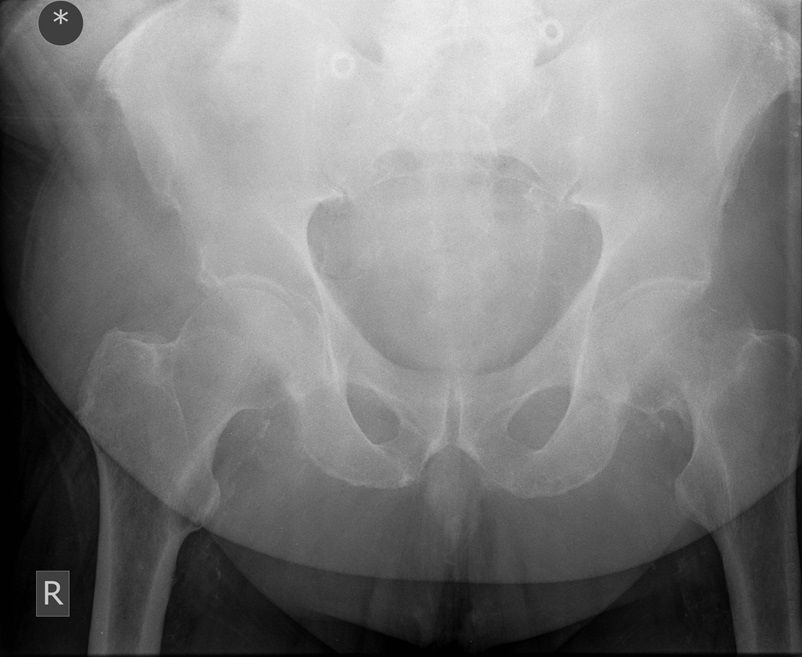

I was hoping you would partake in a study we are doing. We want to establish if there is any bias when deciding an operation based on the radiograph. We understand that the NICE guidelines state that the patient management for hip surgery should not be based on the radiographic findings; rather it should be based on defined criteria. However with that aside what we are requesting is that you look at the film + decide what operation either THR or Hemiarthroplasty. Click the dot + select answer.

Question 4

Question

Which operation would you perform?

Answer

• THR

• Hemiarthroplasty